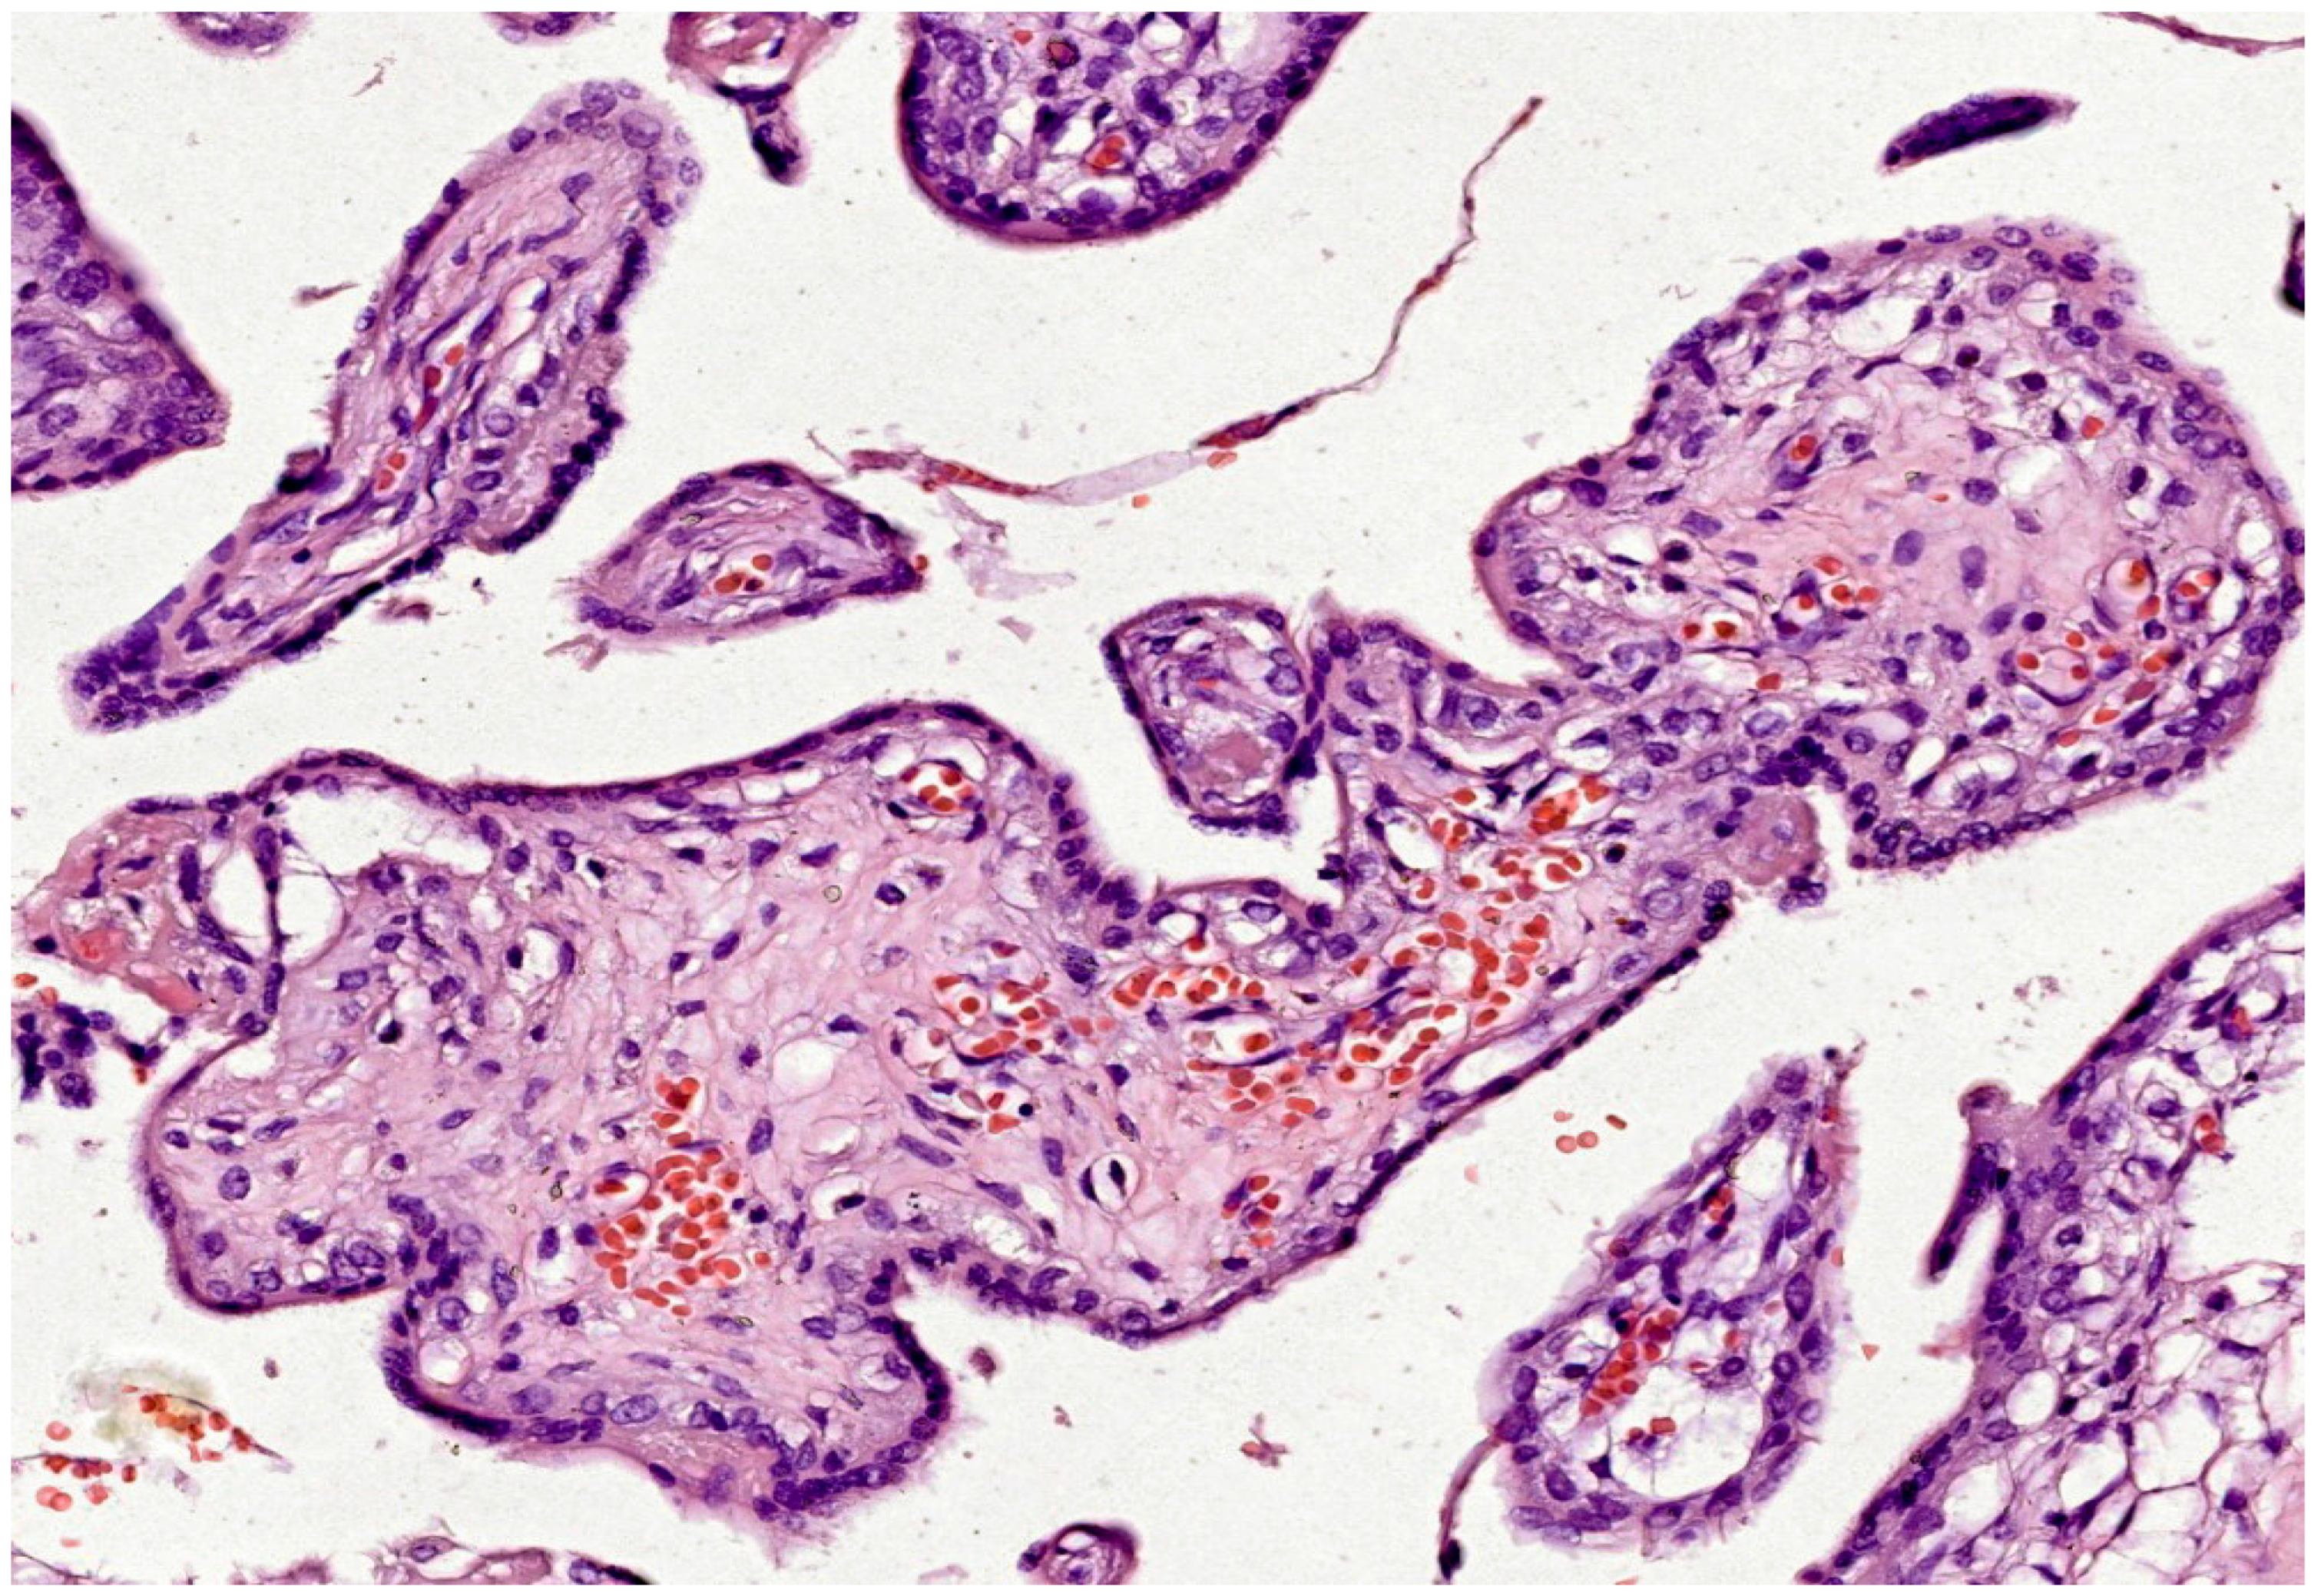

- Immature intermediate villi: These are peripheral, immature, bulb-shaped continuations of stem villi. They have a looser or reticular stroma. Hofbauer cells, more prominent blood vessels and a discontinuous layer of cytotrophoblast cells are noted in these villi. The outer layer, the syncytiotrophoblast, remains continuous throughout development. Immature intermediate villi form the basis for growth of the villous "tree". It is considered that maternal-fetal exchange occurs mainly in these villi during the first and second trimesters, until terminal villi differentiate [58].

| Pathology | Role of Oxidative Stress | Histological Features |

|---|---|---|

| Fetal Vascular Malperfusion | - Causes endothelial damage leading to thrombosis - Increases inflammation and coagulation |

- Villous stromal-vascular karyorrhexis - Avascular villi - Thrombosis in fetal vessels |

| Chronic Villitis | - Inflammatory cell infiltration increases ROS production - Promotes further inflammation |

- Lymphohistiocytic infiltrate in villi - Destruction of villous architecture - Fibrinoid necrosis |